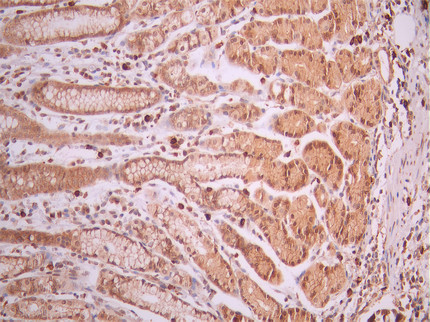

IHC image of CSB-RA268144A0HU diluted at 1:100 and staining in paraffin-embedded human gastric cancer performed on a Leica BondTM system. After dewaxing and hydration, antigen retrieval was mediated by high pressure in a citrate buffer (pH 6.0). Section was blocked with 10% normal goat serum 30min at RT. Then primary antibody (1% BSA) was incubated at 4°C overnight. The primary is detected by a Goat anti-rabbit polymer IgG labeled by HRP and visualized using 0.05% DAB.